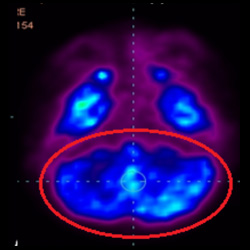

細(xì)胞治療前 PET CT 掃描顯示神經(jīng)組織中的藍(lán)/黑色區(qū)域,表明腦癱引起的大腦損傷。

這證明細(xì)胞療法是治療腦癱兒童安全有效的方法。細(xì)胞療法可以更新大腦損傷的核心,并且可以通過 PET CT 掃描來監(jiān)測大腦的改善情況。這些細(xì)胞療法與標(biāo)準(zhǔn)治療一起促進(jìn)腦癱兒童的生長和改善。